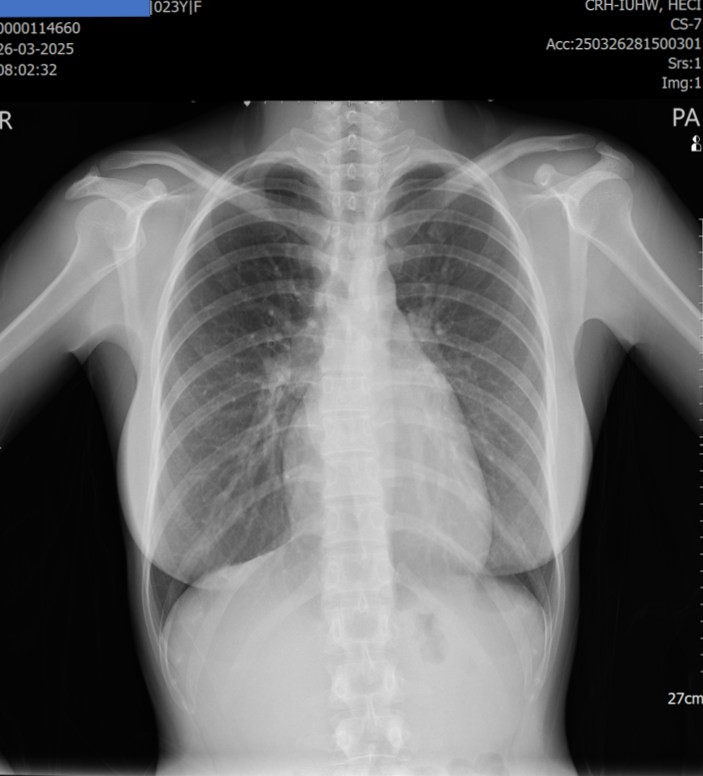

Qua thăm khám lâm sàng, bác sĩ ghi nhận có âm thổi bất thường ở tim, kết quả Xquang ngực thẳng cho thấy hình ảnh bóng tim to.

| Xquang ngực thẳng cho thấy hình ảnh bóng tim to - Ảnh BVCC |